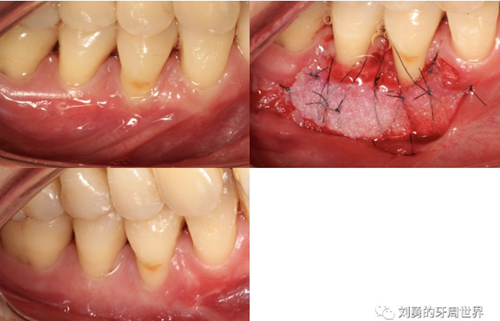

下面這個(gè)是使用楔形手術(shù)切除的牙齦組織進(jìn)行移植的病例,圖片不太清晰,請(qǐng)大家見諒。

下面這個(gè)是我使用國(guó)產(chǎn)的替代品的病例: